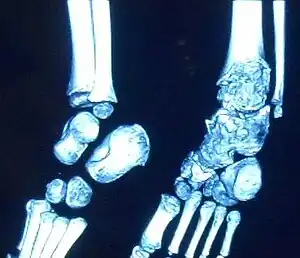

| Trevor disease in a nine-year-old girl: talus | |

This disorder is rare, and is characterised by an asymmetrical limb deformity due to localized overgrowth of cartilage, histologically resembling osteochondroma. It is believed to affect the limb bud in early fetal life. The condition occurs mostly in the ankle or knee region and it is always confined to a single limb. This usually involves only the lower extremities and on medial side of the epiphysis. It is named after researcher David Trevor.[1]

Trevor disease was first described by the French surgeon Albert Mouchet and J. Belot in 1926. In 1956, the name "dysplasia epiphysealis hemimelica" was proposed by Fairbank.[1] The usual symptoms are the appearance of an osseous protuberance, on one side of the knee, ankle or foot joint which gradually increases Radiologically,[14] the condition shows a nonuniformity of growth and multiple unconnected ossification centers around the epiphyses.[8]